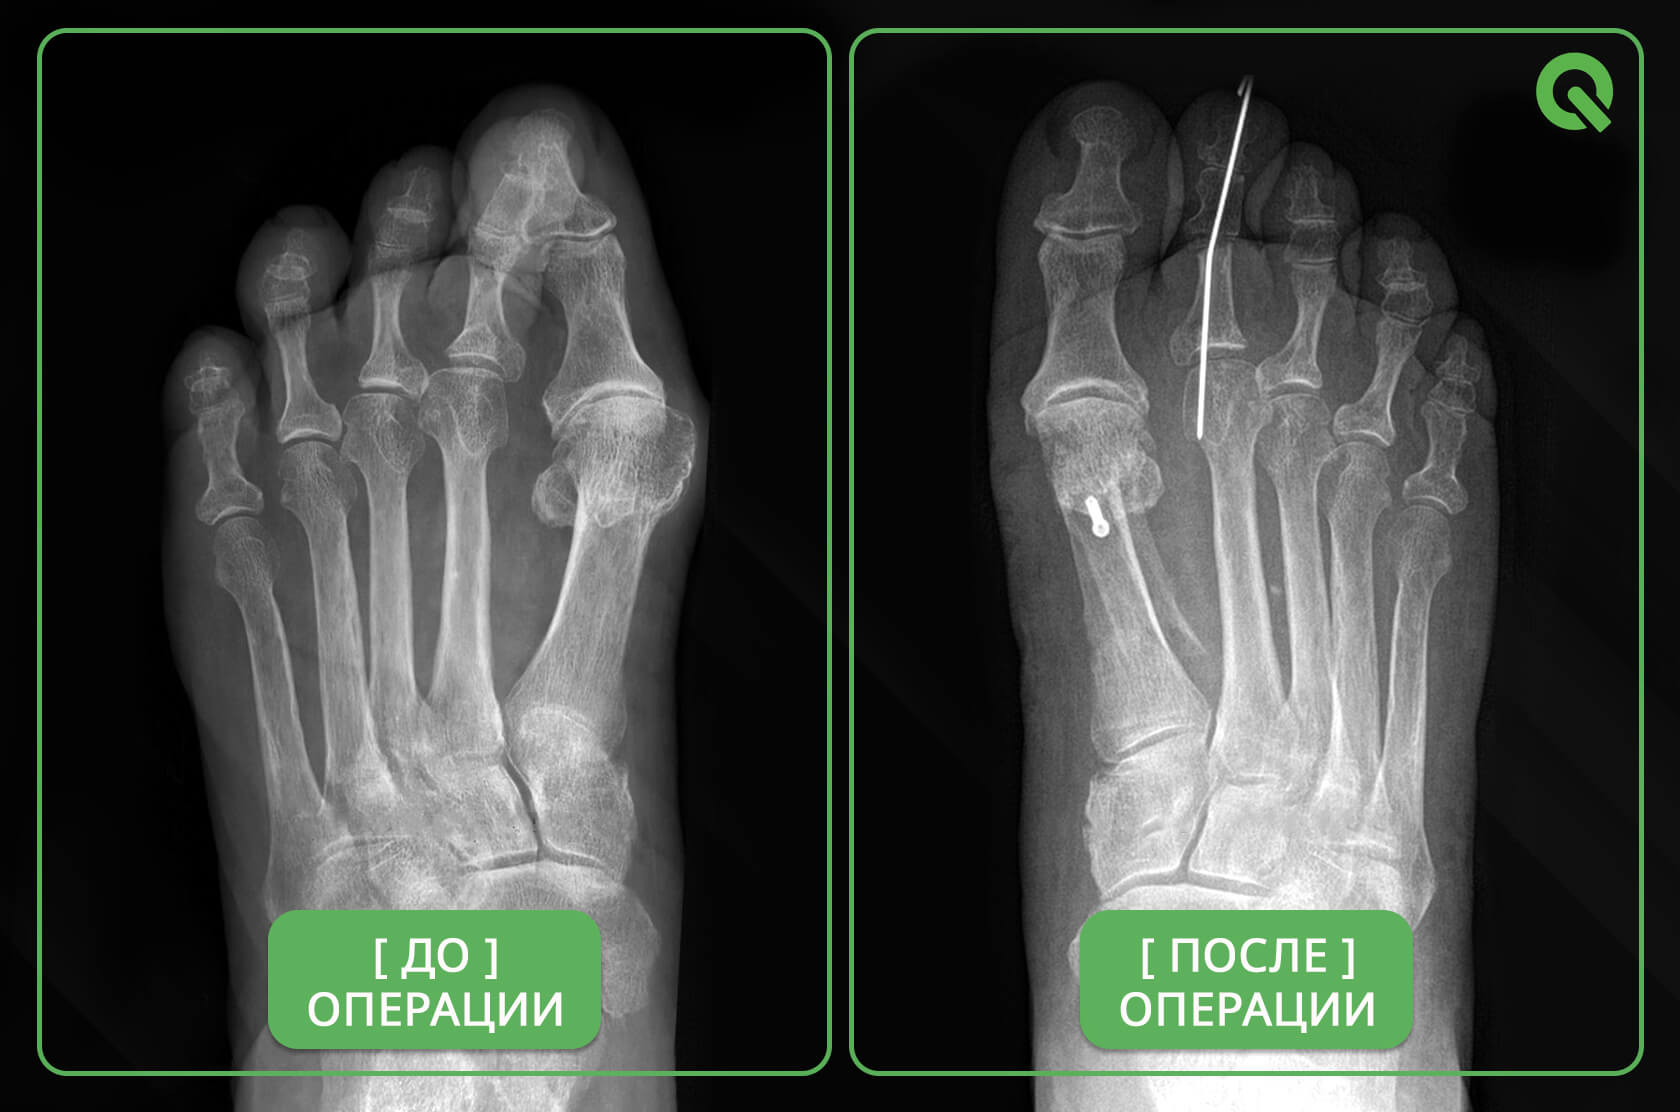

Операция Вальгусная Деформация Фото

Операция Вальгусная Деформация Фото 113 фотографий